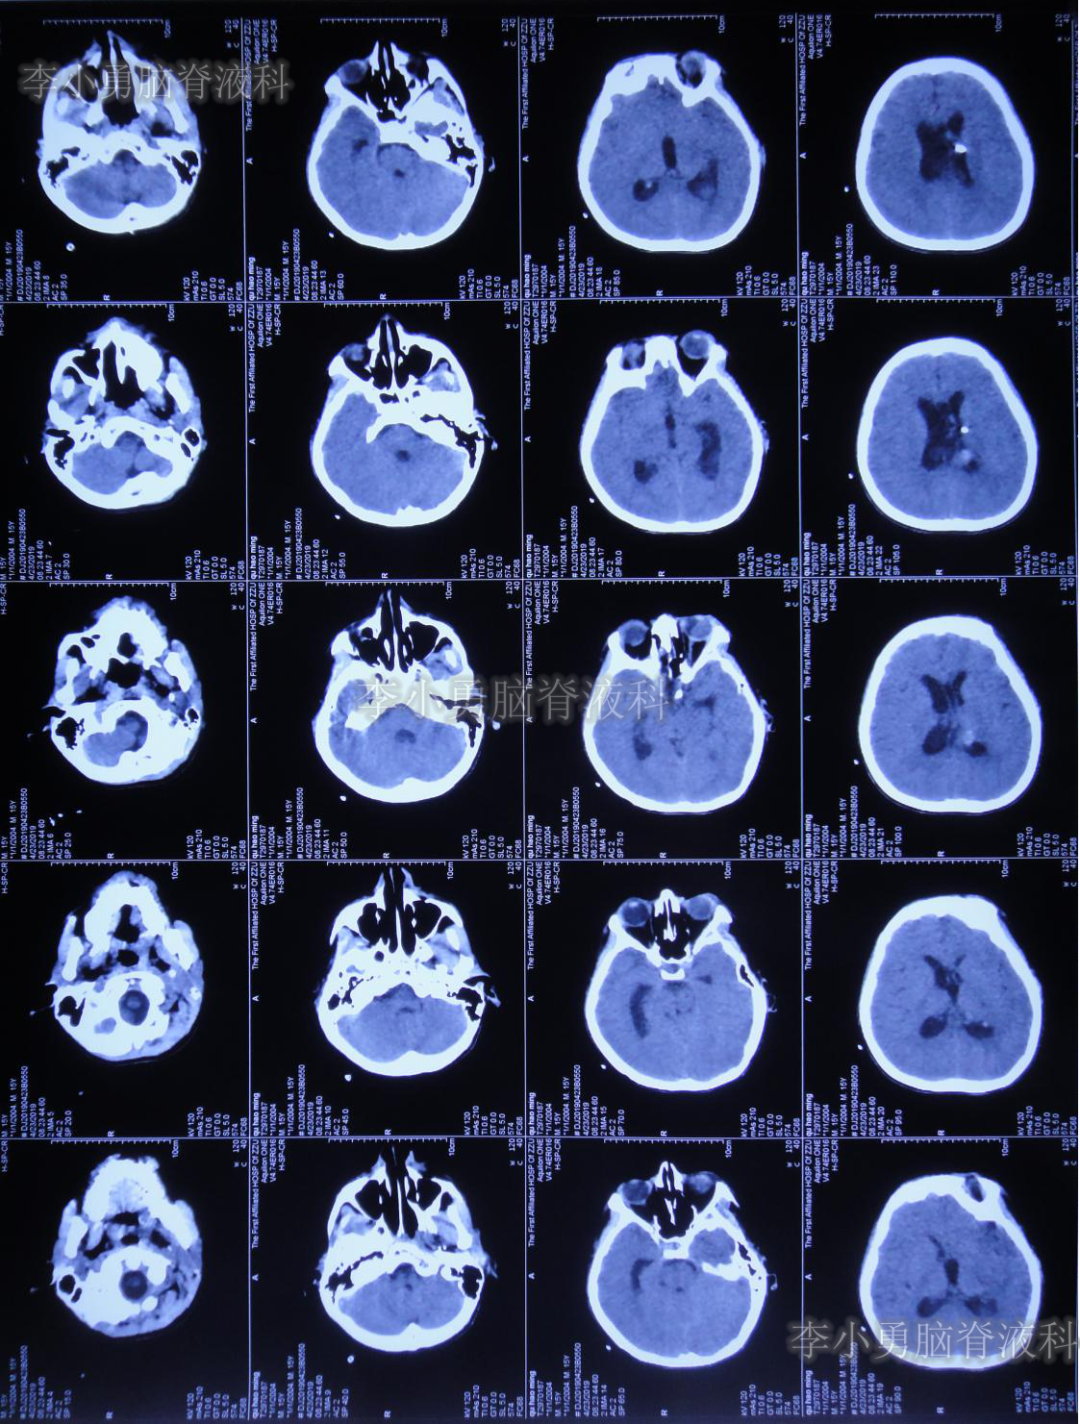

次日即2019年4月2日给予行腰椎穿刺术,引流出血性脑脊液;但腰椎穿刺术刚结束突然晕厥,再次复查头颅CT(图-4):脑室内出血量较前明显增多,四脑室及中央导水管铸形。

图-4:2019年4月2日头颅CT:脑室内积血明显增多

当日急诊进行了脑室外引流术(第二次行脑室外引流术),医生感病情复杂,建议转上级医院治疗。

次日2019年4月3日(脑出血后8天),转至河南省郑州市某三甲医院;入院当日头颅CT(图-5)及CTA(图-6)检查结果:出血量较昨日无增加,动脉血管未见明显异常。

图-5:2019年4月3日头颅CT:出血量无增加

继续给予脑室外引流1周后即2019年4月11日,再次复查头颅CT(图-7):脑室内积血明显减少,脑室不大。

图-7:2019年4月11日头颅CT:脑室内积血明显减少